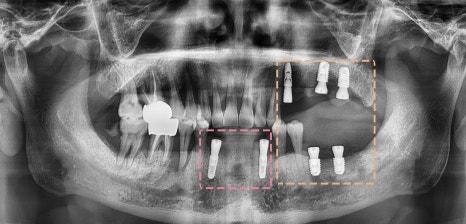

치료 계획은

- 잔존 치근 : 발치

- 심한 치주염 & 뿌리 끝 염증 : 발치 후 임플란트

- 치태 및 치석 : 스케일링으로 계획했습니다.

전체적으로

치태와 치석이 많아서

스케일링과 치주치료를 하기로 했으며

상태가 좋지 못한 부위는

발치 후 임플란트 를 식립하기로 했습니다.

컴퓨터 시뮬레이션으로

픽스쳐가 심겨질 위치를 파악하고

임플란트 를 심기로 했습니다.

앞니부터 심고

왼쪽 위아래 –>오른쪽 위아래 순으로 진행했는데

수술 기간 동안

환자께서 음식을 먹을 수 있도록

단계별로 임플란트 를 식립하게 되었습니다.